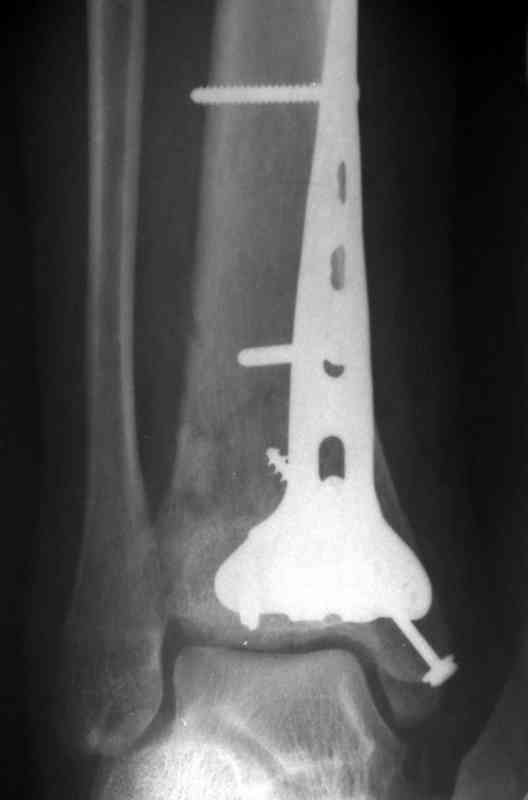

Посылаю результат лечения предыдущего больного через год.

С уважением Дрягин